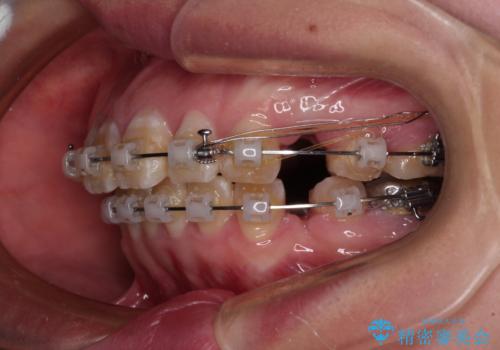

- クリアブラケット

- 2年4ヶ月

- 口元の閉じにくさと、前歯のでこぼこの歯並びを気にして来院された患者様です。

口元を積極的に引っ込めるために、上下左右の小臼歯計4本を抜歯することとしました。

4本の歯を抜歯したことで、飛び出していた口元が引っ込み、横顔が大きく改善されました。